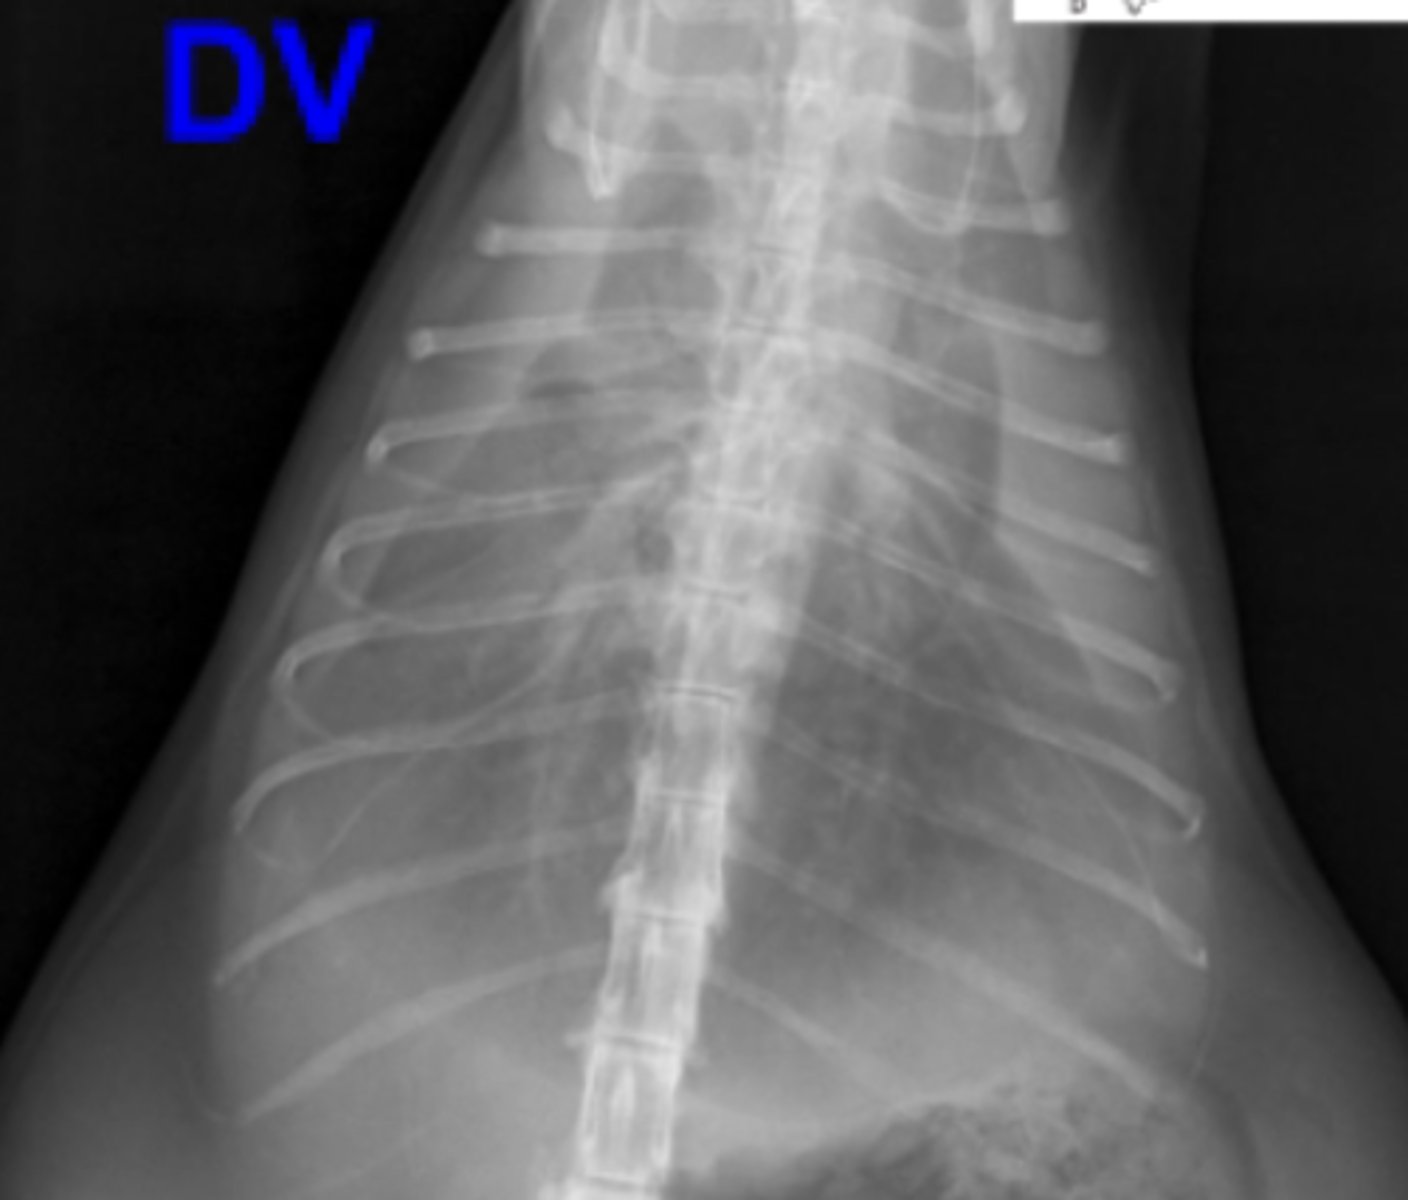

efusión pleural

patología: